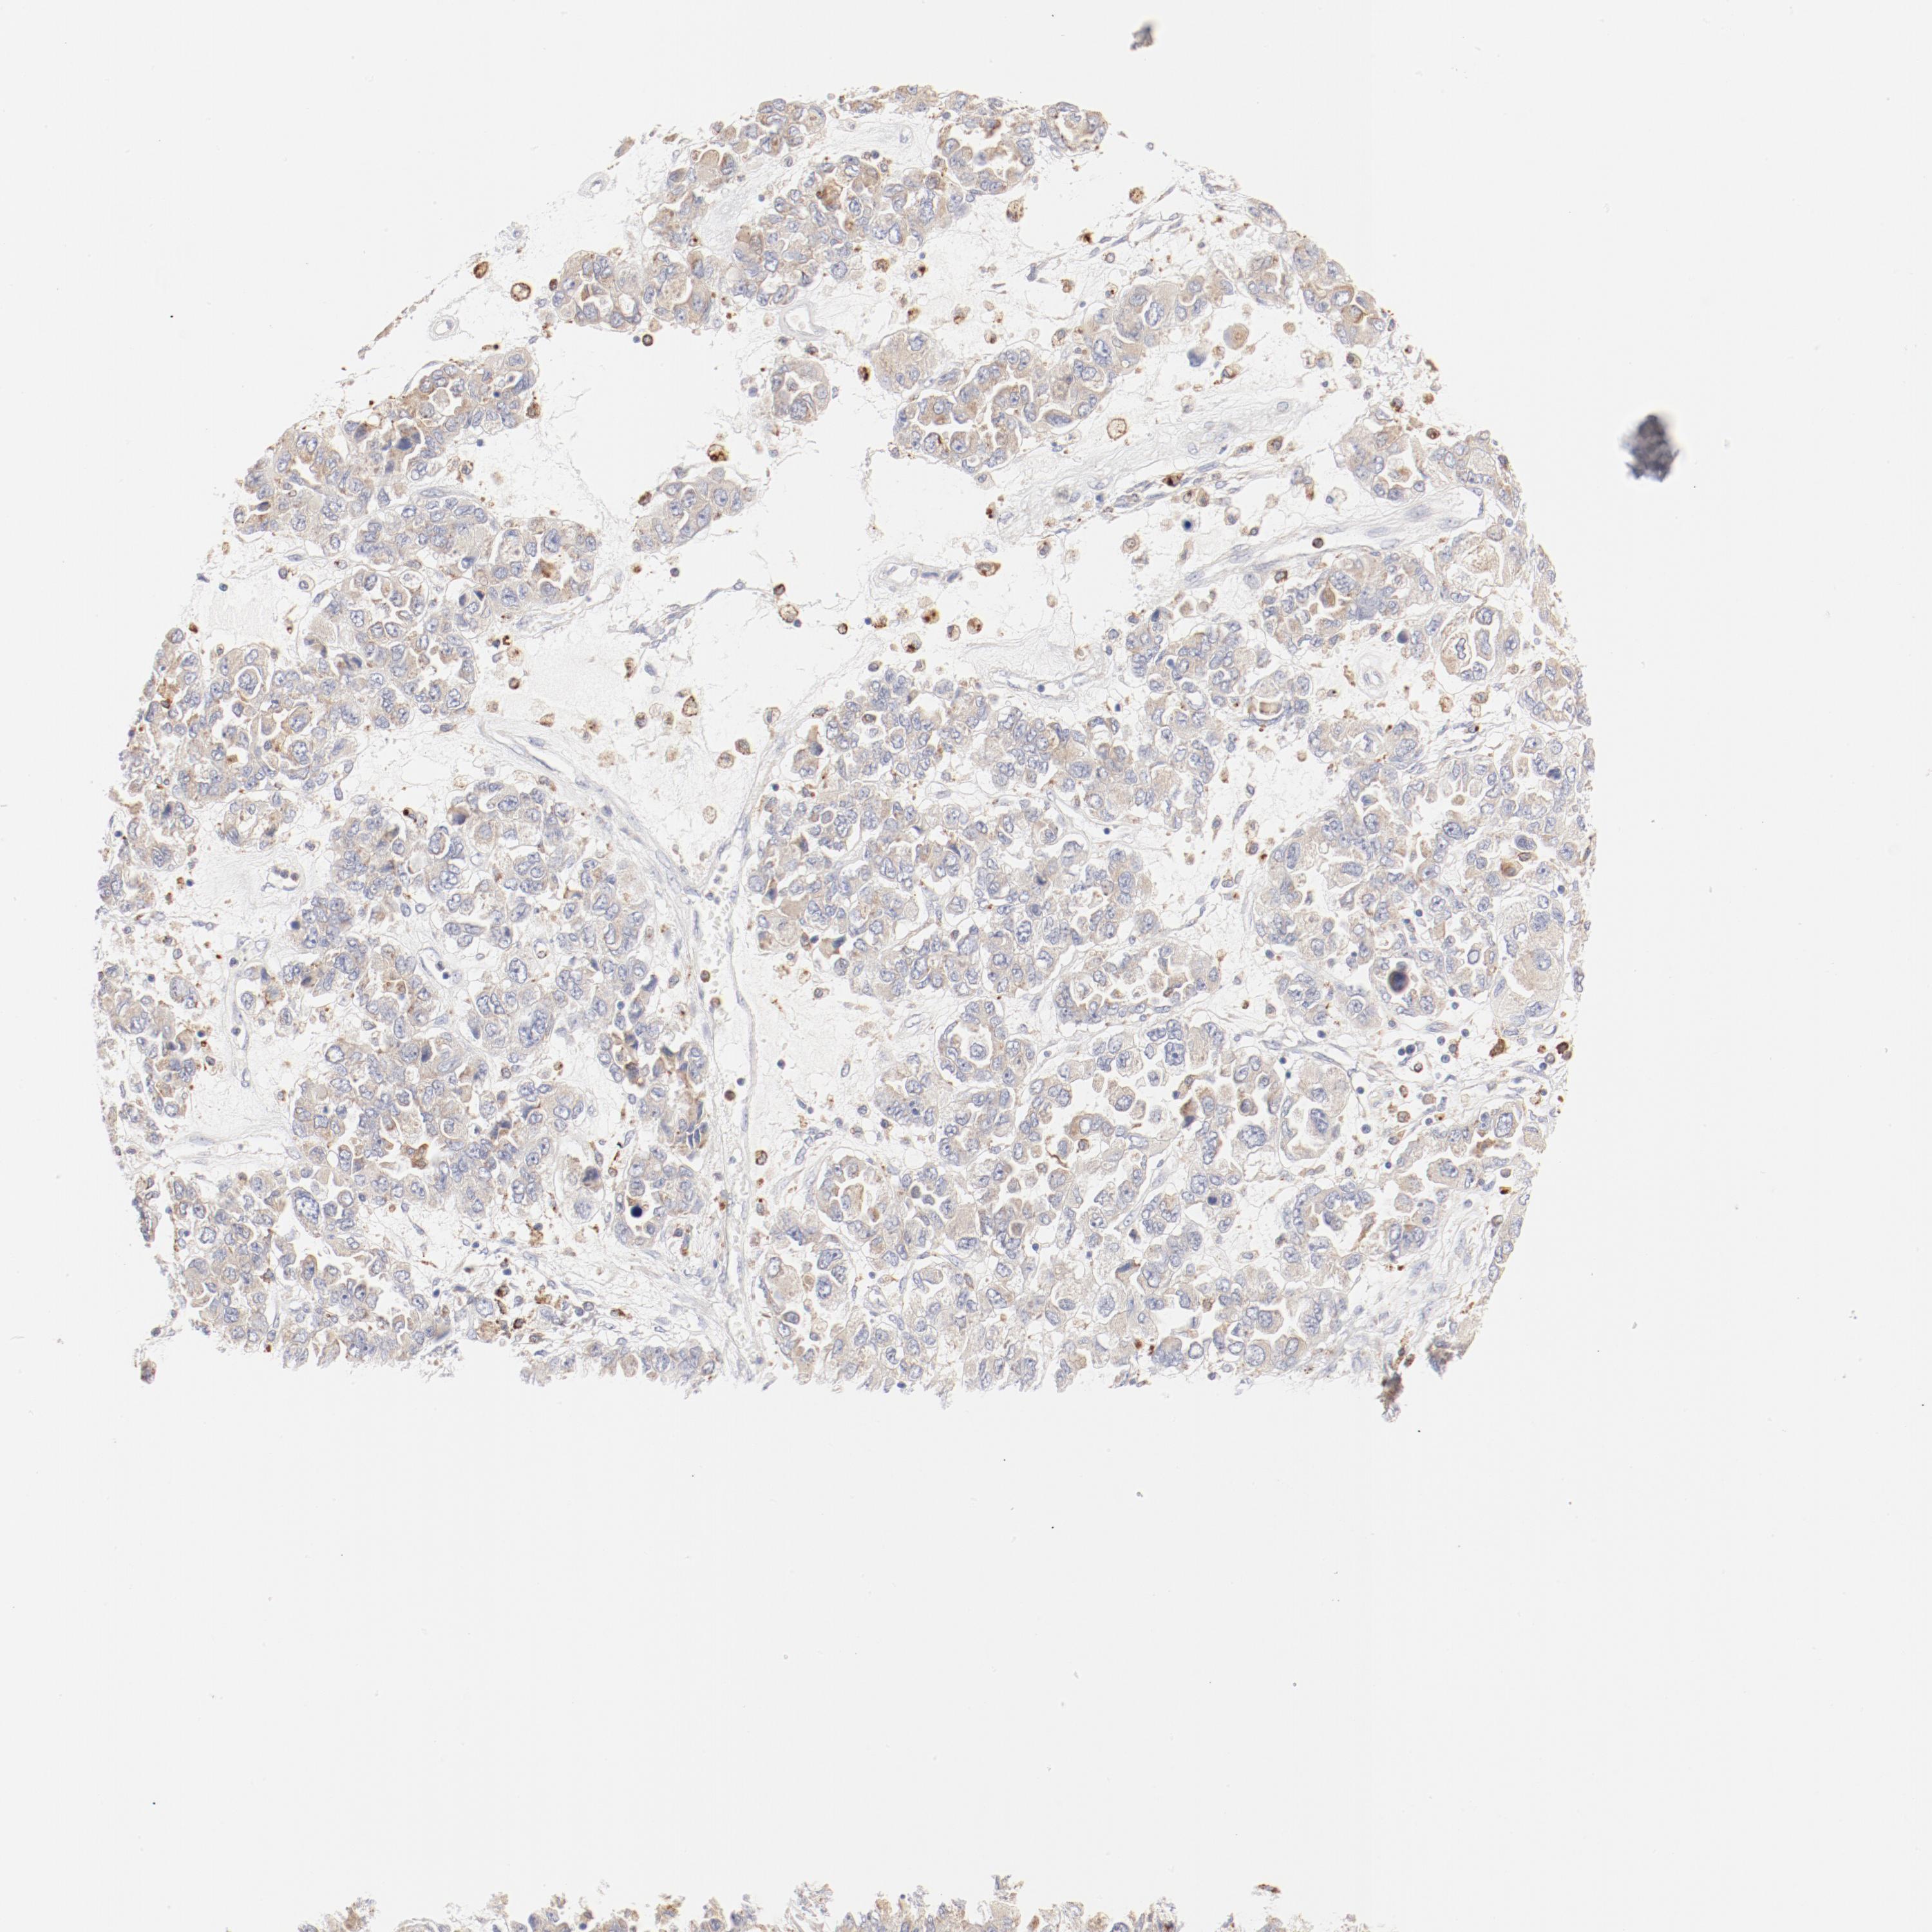

OVARIAN CANCER - Protein expressioni

A mouse-over function shows sample information and annotation data. Click on an image to view it in a full screen mode. Samples can be filtered based on level of antibody staining by selecting one or several of the following categories: high, medium, low and not detected. The assay and annotation is described here.

Note that samples used for immunohistochemistry by the Human Protein Atlas do not correspond to samples in the TCGA dataset.

Antibody stainingi

Antibody staining in the annotated cell types in the current human tissue is reported as not detected, low, medium, or high, based on conventional immunohistochemistry profiling in selected tissues. This score is based on the combination of the staining intensity and fraction of stained cells.

Each image is clickable and will lead to virtual microscopy that enables deeper exploration of all samples and also displays staining intensity scores, fraction scores and subcellular localization as well as patient and tissue information for each sample.

Antibody HPA003524

Antibody CAB000458

Staining

High

Medium

Low

Not detected

Intensity

Strong

Moderate

Weak

Negative

Quantity

>75%

75%-25%

<25%

None

Location

Nuclear

Cytoplasmic/membranous

Cytoplasmic/membranous,nuclear

Cystadenocarcinoma, mucinous, NOS

Carcinoma, endometroid

Cystadenocarcinoma, serous, NOS